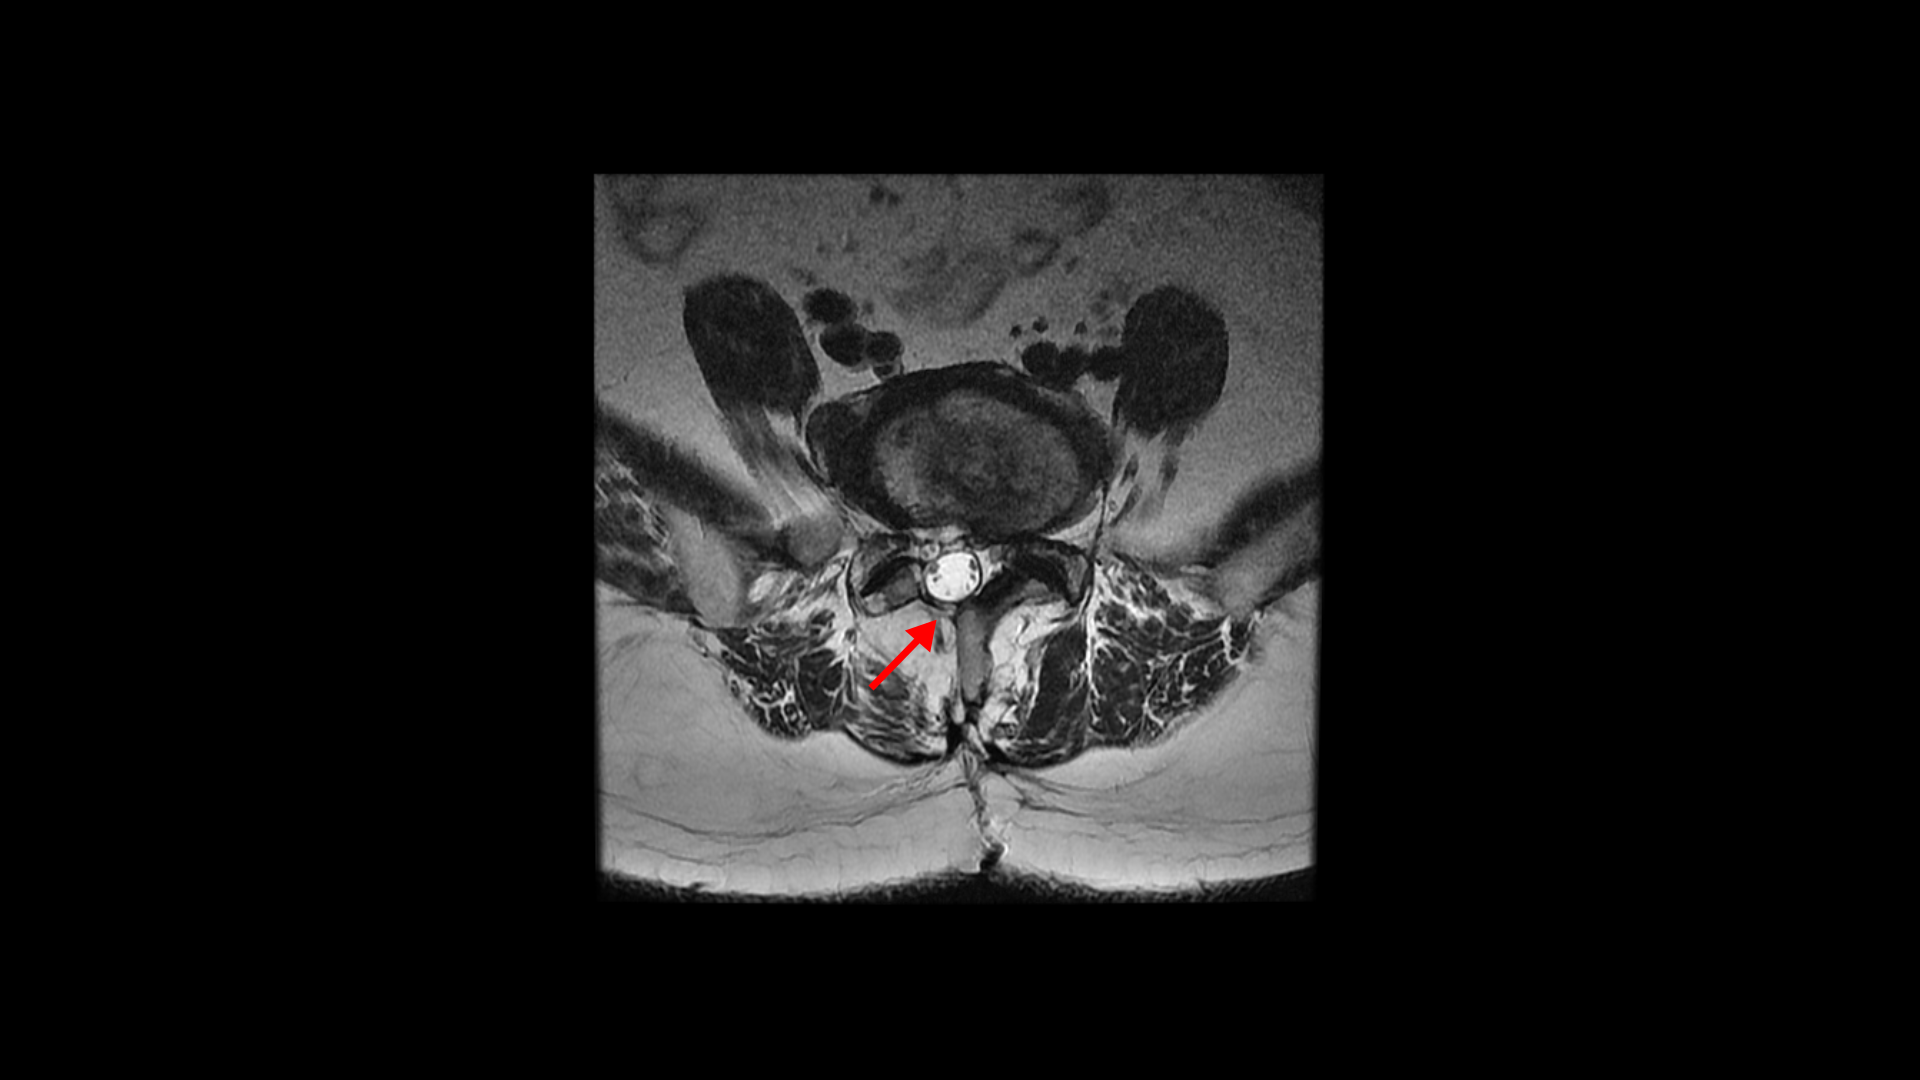

그런데 유합술 후 오른쪽 다리의 증상은 좋아졌으나 상대적으로 괜찮았던 왼쪽 다리에 심한 방사통과 마비 증상이 생겼습니다. 수술 후에 집도의로부터 수술은 잘 됐으나 수술한 자리가 부어있어서 신경을 눌러서 그럴 거니까. 1년 이상 기다리면 좋아질 것이라는 얘기를 들었습니다. 그런데 저희 모커리한방병원은 디스크나 협착증, 전방전위증 등으로 오랫동안 다리 방사통을 겪은 환자분들 중 수술받은 분들께 수술 후 남아있거나 새로 생기는 방사통이나 마비 증상은 회복을 위해 1년씩 혹은 그 이상 오래 기다릴 필요가 없다고 말씀 드리고 있습니다. 보통은 수술집도의 분들의 설명은 수술 전에 오래 눌려있던 신경이 다시 회복되는데 시간이 오래 걸리기 때문에 기다려야 한다고 얘기하는데, 저희 관점에서는 척추 수술 후 회복되는데 시간이 오래 걸리는 이유가 전혀 다릅니다.

실제로 수술을 잘해서 눌린 신경을 성공적으로 잘 풀어준 후에도 통증이나 마비가 남아있거나 안 아프던 다리에 통증이 새로 생기는 환자들이 많습니다. 그런데 다시 말씀 드리지만 수술 전 근육의 문제가 전혀 해결되지 않은 상태에서 수술을 하면 눌린 신경은 풀어주지만, 근육의 문제는 전혀 해결이 안 된 상태이고 또 수술 시 근육의 일부를 찢고 자르면서 근육에는 추가적인 손상을 주게 되니까 근육 문제는 오히려 더 심해질 수도 있습니다. 그래서 수술 후에도 다리 저림이나 마비 증상이 남아있거나 없던 증상이 새로 생길 수 있는 겁니다.

수술 병원에서는 수술로 눌린 신경을 잘 풀어주었으나 신경이 오래 눌려 있었기 때문에 신경이 회복되려면 길게는 1년 이상 기다려야 한다고 설명하지만 저희 생각은 완전히 다릅니다. 근육 상태가 상대적으로 좋았던 사람들은 금방 풀리는 사람도 있을 수 있지만 상태가 많이 안 좋았던 사람들일수록 빠른 시일 내에 자연적으로 쉽게 해결이 되지 않습니다. 이런 환자분들은 직접적으로 근육을 직접 치료해서 뭉치고 단축되고 굳어있는 문제들을 직접 해결해 주면 훨씬 더 빠른 회복이 가능합니다. 근육을 직접 치료하는 방법은 다양합니다. 침, 약침, 봉침, 부항, 추나요법, 도수치료, 재활 운동 등 다양한 방법으로 근육을 직접 치료합니다. 이 환자분도 역시나 수술로 신경 감압은 잘 되었지만 엉덩이와 다리 근육들이 극심하게 뭉쳐있는 상태였습니다.